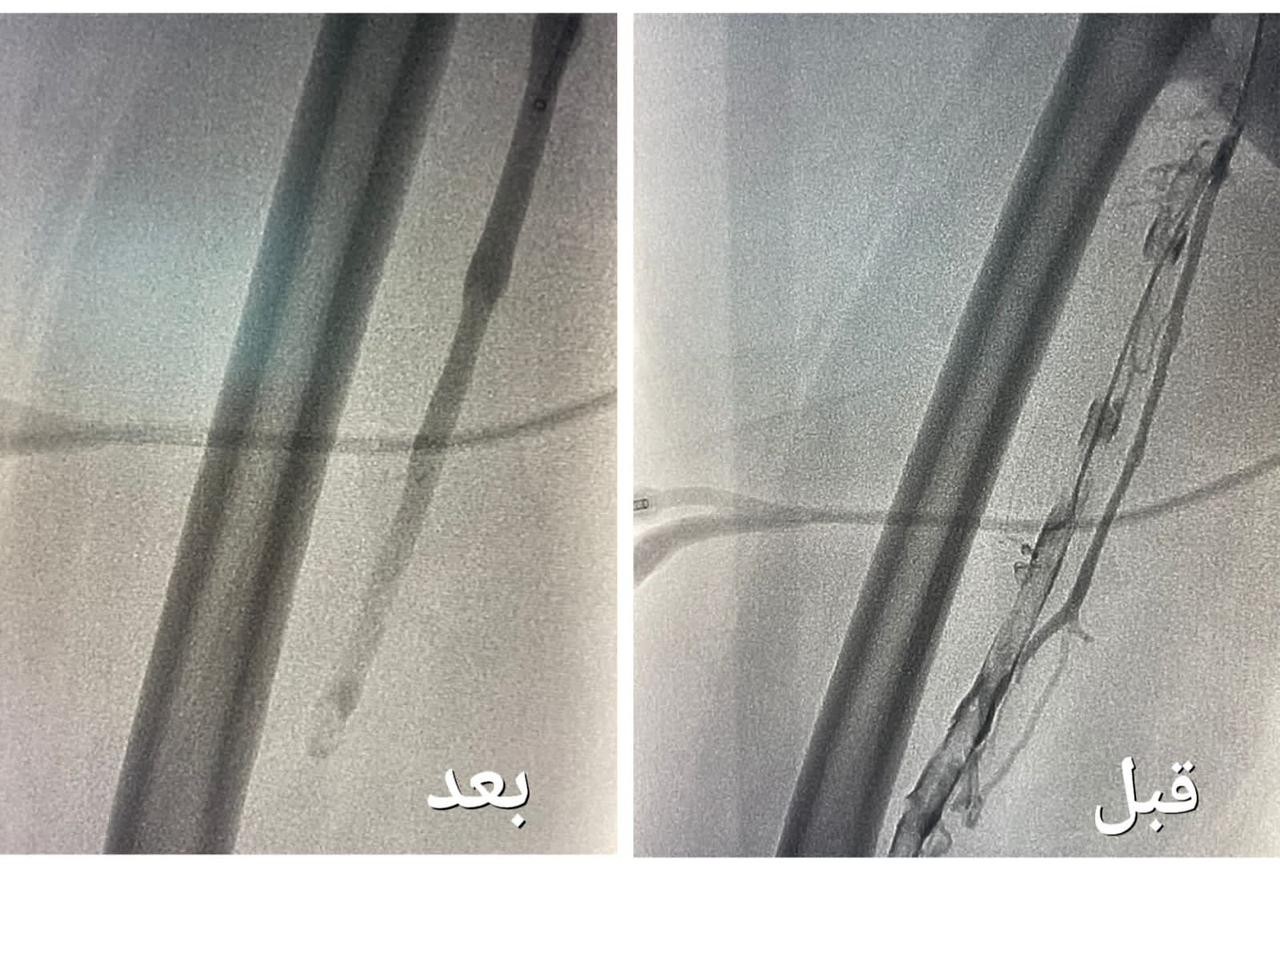

تمكن فريق وحدة الأشعة التداخلية بمجمع الملك عبدالله بجدة من إنهاء معاناة حاجّة هندية تبلغ من العمر ٦٧ عاماً ، و كانت الحاجّة تعاني من جلطة وريدية من مستوى الكاحل إلى مستوى أوردة الحوض الأيمن ، و انتفاخ كامل في القدم مع عدم القدرة على المشي .

وأوضحت "الصحة" أنه بعد  إجراء الفحوصات الطبية و الكشف تبين وجود جلطة وريدية من مستوى الكاحل إلى مستوى أوردة الحوض الأيمن ، و انسداد كامل في أوردة القدم اليمنى حتى الحوض ، قرر بعدها الفريق الطبي تنويم المريضة و التنسيق مع فريق وحدة الأشعة التداخلية بشكل عاجل لدراسة الحالة و معالجتها ،  و وضع الخطة العلاجية ، لنقلها إلى غرف عمليات الأشعة لإجراء عملية بإستخدام جهاز إزالة الجلطات تحت التخدير الموضعي و التهدئة الواعية .

وقالت الوزارة إن العملية استغرقت نحو ساعتين ، تكللت _ ولله الحمد_ بالنجاح ، تم فيها تركيب فلتر للوريد الأجوف السفلي لمنع انتقال الجلطات للرئة ، و من ثم الدخول للوريد المتجلط في مستوى الكاحل و حقن مواد مذيبة للجلطات ، و قد استخدمت أجهزة نوعية لمثل هذه الحالات والتي تعمل على سحب الجلطات بعد إذابتها و توسعة الأوردة بالبالون لإعادة جريان الدم .